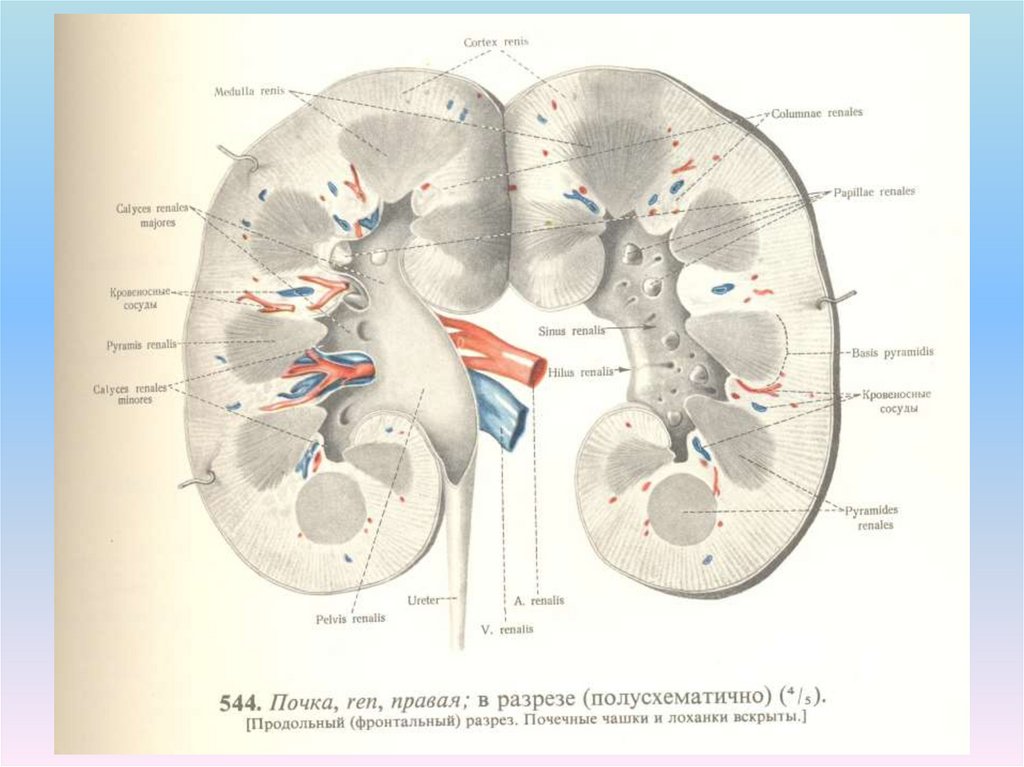

Интраренальная лоханка: рентгеновские снимки и примеры